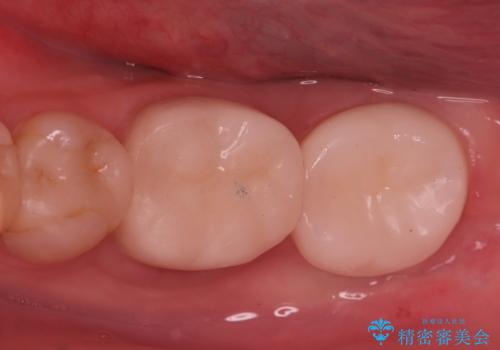

発見の難しい虫歯。根管治療から被せもの治療

- 定期検診にて被せものと歯との隙間に虫歯を発見した患者様です。

根管治療から被せもの治療(ベレッツァ)まで行いました。(根管治療は林院長に依頼)

妥協せずにすべての治療を行うことで最終的な被せものの適合を高める事ができます。